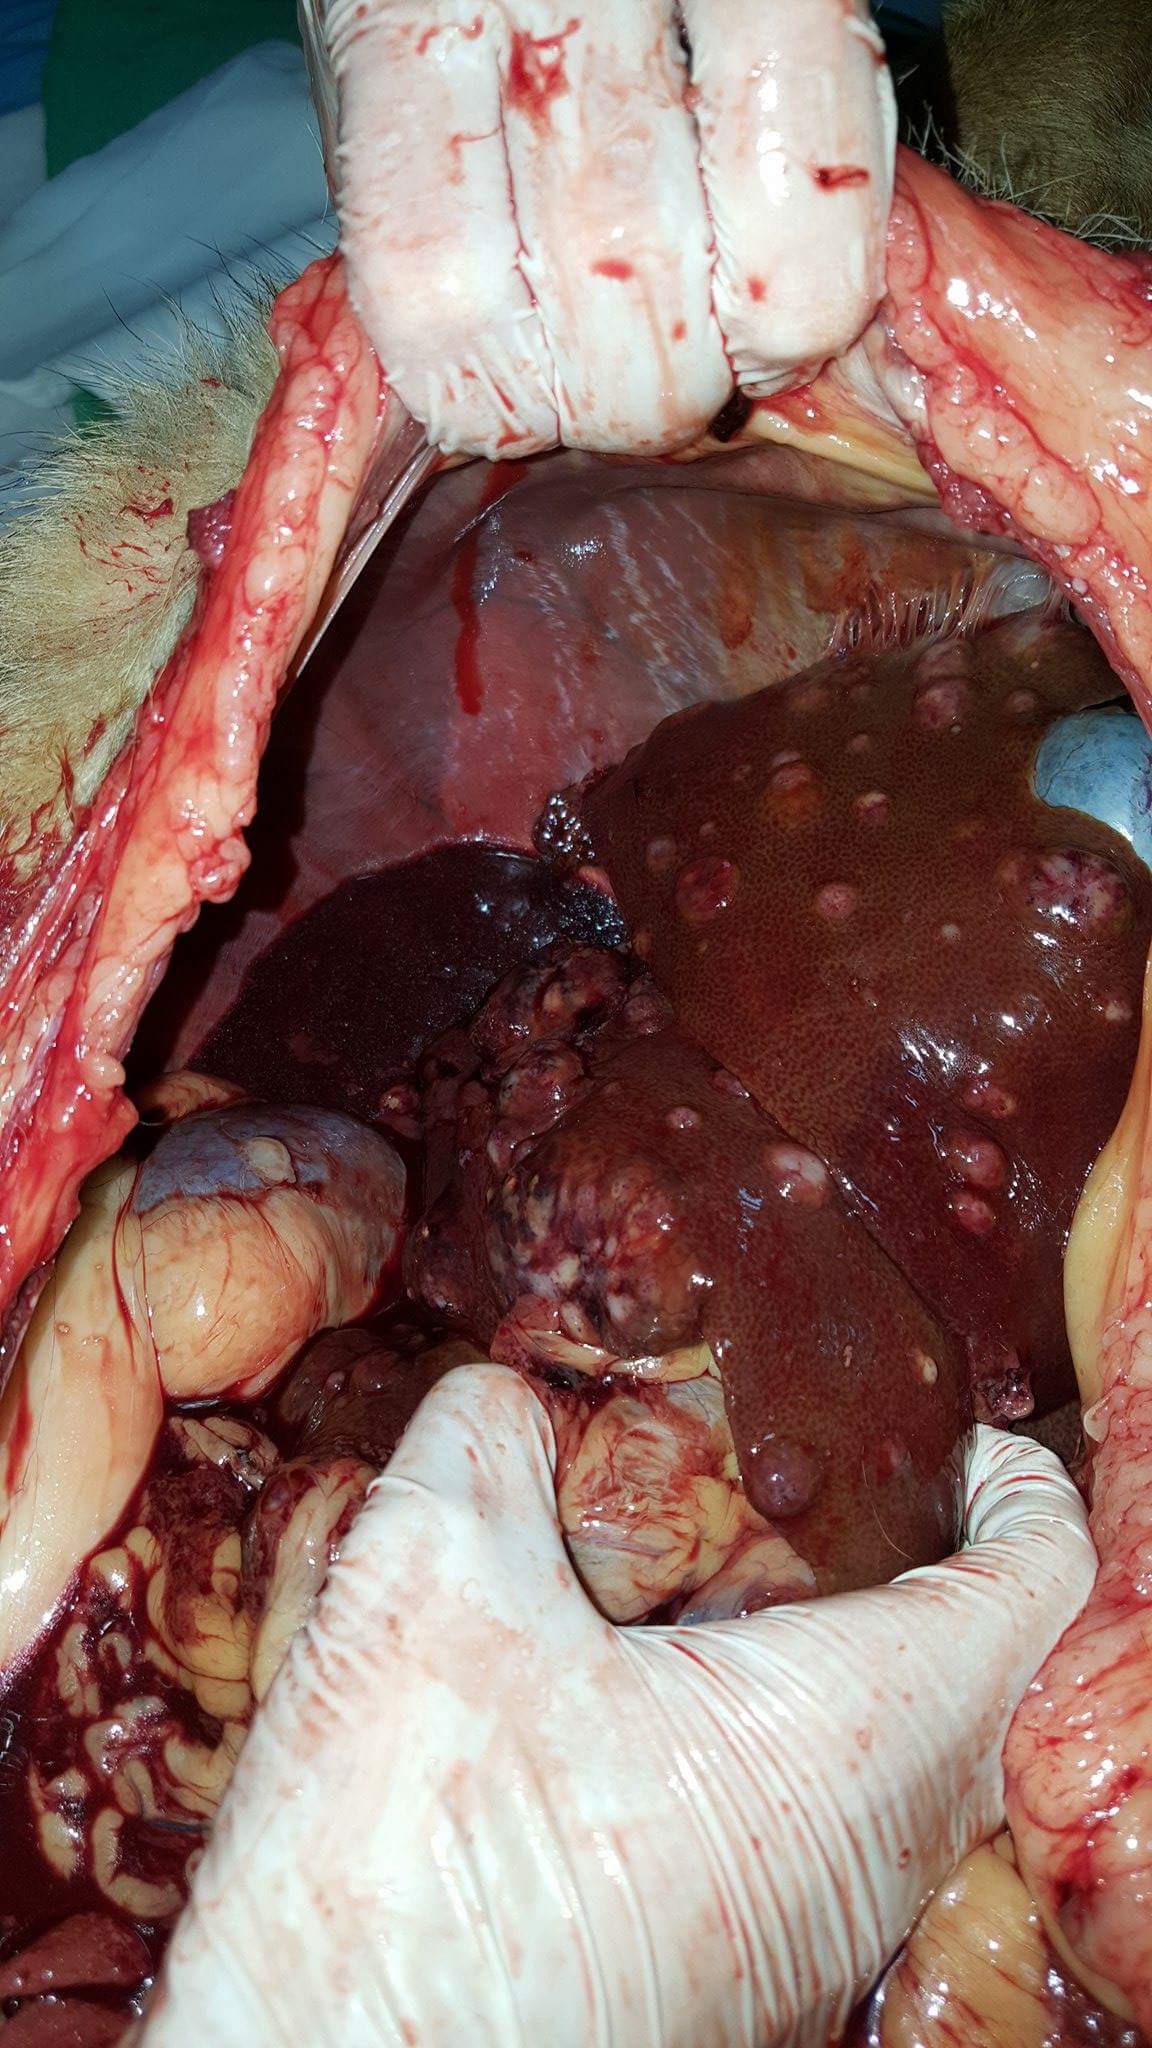

Czerwiec

W USG płyn w j. brzusznej w dużej ilości, decyzja o eutanazji, sekcja wykazała: krwotok z guzów wątroby

zmianę obejmującą trzon i plat lewy trzustki- twardą, litą z obszarem martwicy w centrum, widać na zdjęciu brązowawy obszar we wnętrzu przekrojonego guza